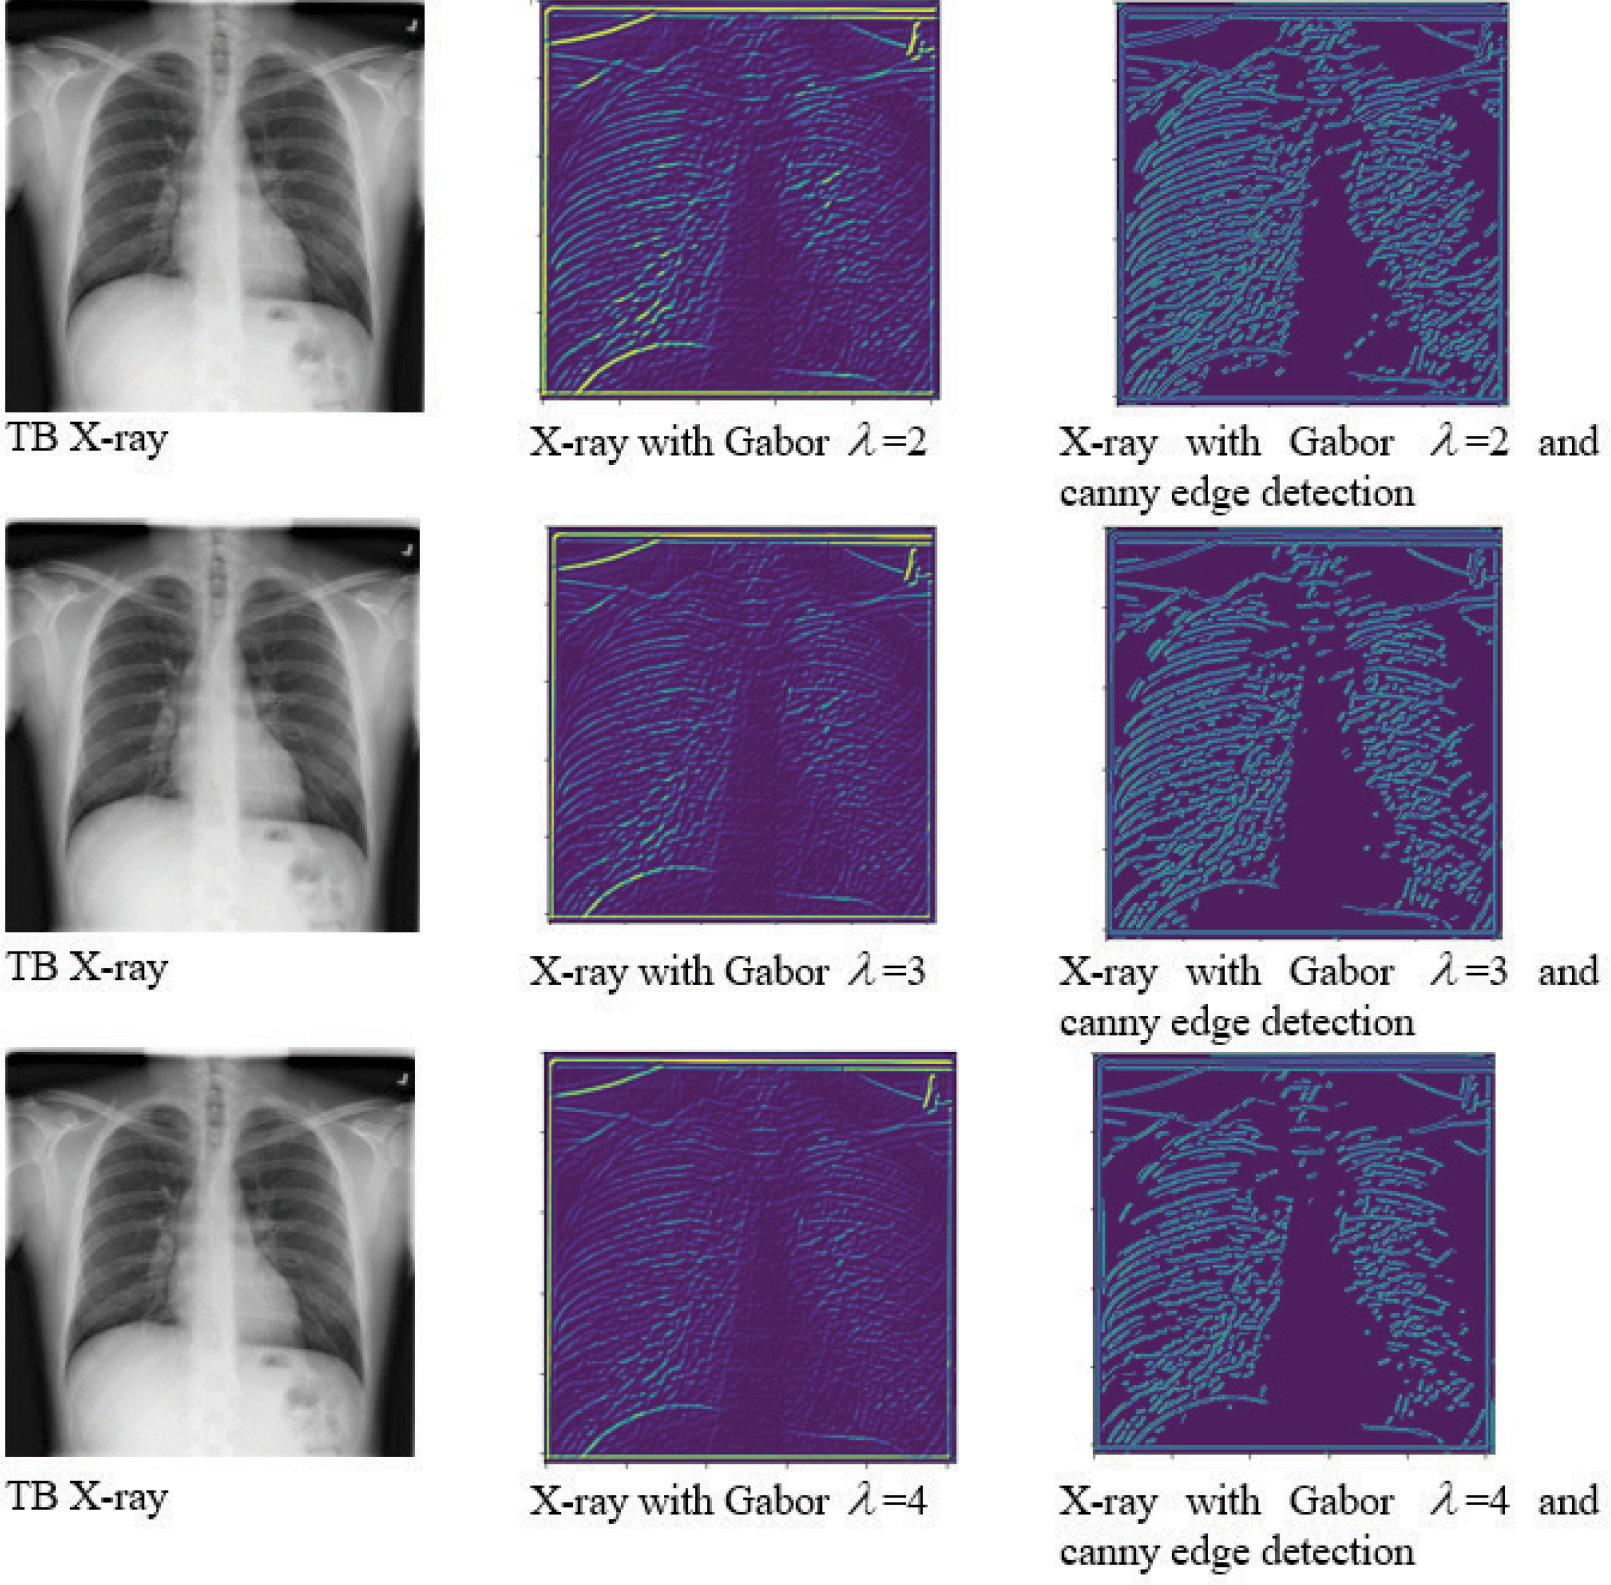

The pre-trained deep convolution network architectures were applied for the classification of TB in this study. DesnseNet169 and MobileNetV2 were used as pre-trained deep learning models to extract deep features [23]. For this, the layers of densenet was established as non-trainable. The model would use pre-trained weights to extract features from input images, and then train a custom output layer to classify features. Similarly, MobileNetV2 was setup with frozen layers for using as feature extractor. In addition to the default feature extraction, Gabor filter extracted more features. It was also possible to improve the model accuracy and efficiency by incorporating Canny edge detection, mainly when an expert radiologist could not analyze the features. The Gabor filter is a complex wavelet filter used to capture fine-grained textures [32]. It also helps in distinguishing TB from other lung issues. 2D Gabor filer is defined in Eq. 1:

gx,y=expx12+y2+y122σ2cos2Πx1λ+φ 1

where x,y are the spatial coordinates of input image, l is the wavelength, s is the standard deviation, and ϕ isthe phase offset. To know the details of normal and TB-infected images, Gabor filter was applied with three value of lambda (l), followed by Canny edge detection. Figure 3 shows the details of the images.

Figure 3

Sample image output after applying Gabor filter and Canny edge detection